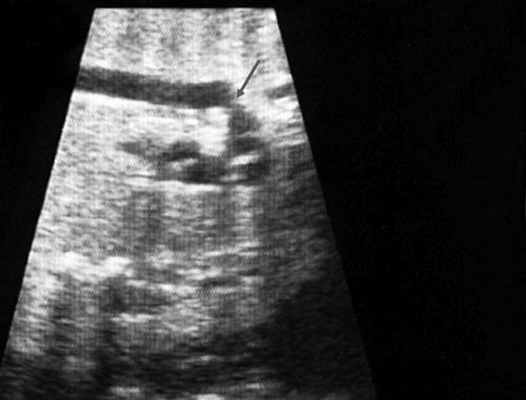

Согласно "теории дуктальной ткани" коарктация аорты возникает в результате миграции гладких мышечных клеток протока в предуктальную аорту, с последующей констрикцией и сужением просвета аорты [4]. При формировании коарктации аорты в области перешейка сохраняется сужение различной протяженности и формы (рис. 2, 3). Наиболее часто это проявляется в виде локальной перетяжки, выше или ниже которой диаметр аорты сохраняется в норме.

Рис. 2. Ультразвуковое исследование восходящего отдела, дуги и нисходящего отдела аорты. Стрелкой указано место сужения.

Известно, что диагноз данного порока сердца опирается на прямой признак - визуализацию места сужения аорты, и, возможно, расширение проксимального отдела аорты. Однако четко визуализировать участок сужения аорты у плода достаточно трудно и удается только в единичных наблюдениях. Порок можно увидеть лишь тогда, когда имеется уменьшение диаметра перешейка аорты более чем на 1/3 по сравнению с нормой для каждого срока беременности (см. рис. 2, 3).